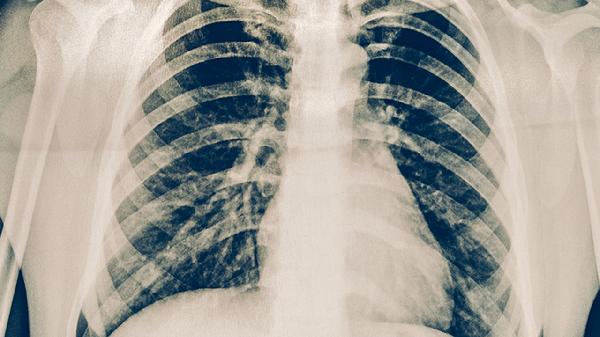

支气管肺炎可遵医嘱使用阿莫西林克拉维酸钾片、盐酸左氧氟沙星胶囊、注射用头孢曲松钠、氨溴索口服溶液、布地奈德吸入气雾剂等药物。支气管肺炎多由细菌、病毒等病原体感染引起,需根据病原学检查结果选择针对性药物,同时配合止咳化痰、解痉平喘等对症治疗。